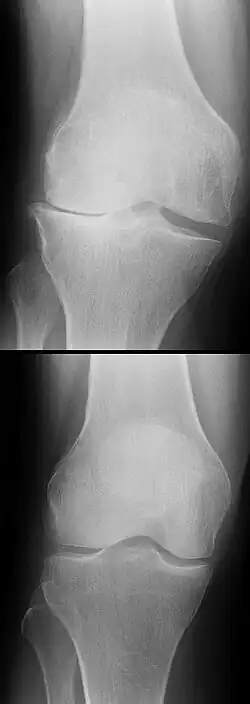

Die Diagnose kann mit bildgebenden Verfahren – namentlich der Magnetresonanztomographie (MRT, „Kernspin“) – bestätigt werden. Dabei ist allerdings zu beachten, dass die Interpretation der MRT in der Diagnostik eines Kreuzbandrisses zu 20 Prozent falsche Diagnosen liefert. Hier kommt es auf die sogenannten Schnittbilder und die geeignete Positionierung des Kniegelenkes bei der MRT-Untersuchung an. Der Radiologe sollte die genaue Vorgeschichte kennen, die zur Verletzung führte, und auch Erfahrung in der Untersuchung eines verletzten Gelenkes haben, um Fehlbeurteilungen zu vermeiden. Im Vergleich zur MRT liegt die Fehlerquote bei dem erheblich einfacher durchzuführenden Lachman-Test bei nur 10 Prozent.[85][86][87][88] Die MRT ist daher in der Regel zur Diagnose eines vorderen Kreuzbandrisses weniger sensitiv und weniger spezifisch als die klinische Befundung durch einen qualifizierten Orthopäden.[89] Das Ergebnis einer MRT hat nur relativ selten einen Einfluss auf die klinische Entscheidungsfindung[90] und sollte keinen Ersatz für eine sorgfältige Anamnese und Palpation darstellen.[15] Mehrere Studien kommen zu dem Schluss, dass eine MRT nur bei komplizierteren unklaren Knieverletzungen – und dabei eher zum Erstellen einer Ausschlussdiagnose[91] – sinnvoll ist.[92][93]

Röntgenaufnahmen leisten keinen unmittelbaren Beitrag zur Diagnosestellung einer Kreuzbandruptur. Beide Kreuzbänder sind – ob gerissen oder nicht – im Röntgenbild nicht sichtbar. Wird dennoch geröntgt, so kann dies der Diagnosestellung von möglichen knöchernen Begleitverletzungen dienen.